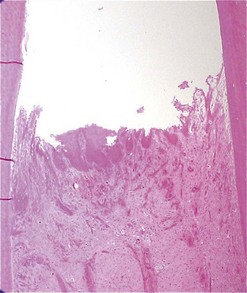

Periodontitis in brachydont species is initiated by the adherence of organic dental plaque and bacteria to teeth.42 Later, the plaque may become calcified to form dental calculus that consists of 70–90 % minerals. A similar finding in equine teeth is illustrated in Figure 10.12. The main component of equine dental calculus is calcite, which has a chalky appearance. In horses, dental calculus most commonly occurs on the lower canine teeth and less commonly on the buccal aspects of the rostral maxillary CT (excluding the wolf tooth),16 and the associated, usually low-grade, periodontal disease usually resolves following removal of the calculus. In general, dental calculus is not a significant problem of equine CT that do not have intercurrent dental disorders.6,9,13 This low prevalence of calculus on equine CT may be due to the prolonged time horses spend masticating, as the prolonged intra-oral movement of fibrous food and saliva during mastication may deter the formation of plaque,42 although equine teeth are covered with an organic pellicle.

image

Fig. 10.12 Decalcified histological section of a CT diastema showing organic plaque deposition (arrow) on the peripheral cementum on both sides of the diastema. (Original magnification ×100).

(Courtesy of Alistair Cox and Sionagh Smith.)